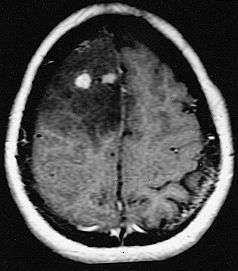

Glioblastoma arising in an astrocytoma. This spinal cord exhibits both a lightly staining microcystic astrocytoma as well as a darkly staining glioblastoma. | |